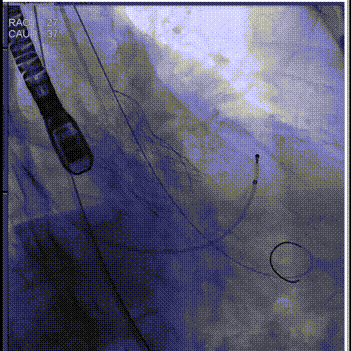

手术过程:

主动脉根部造影

人工瓣膜精准定位

释放工作位评估

术后造影评估

超声显示假体瓣膜形态良好,工作正常,微量瓣周漏。